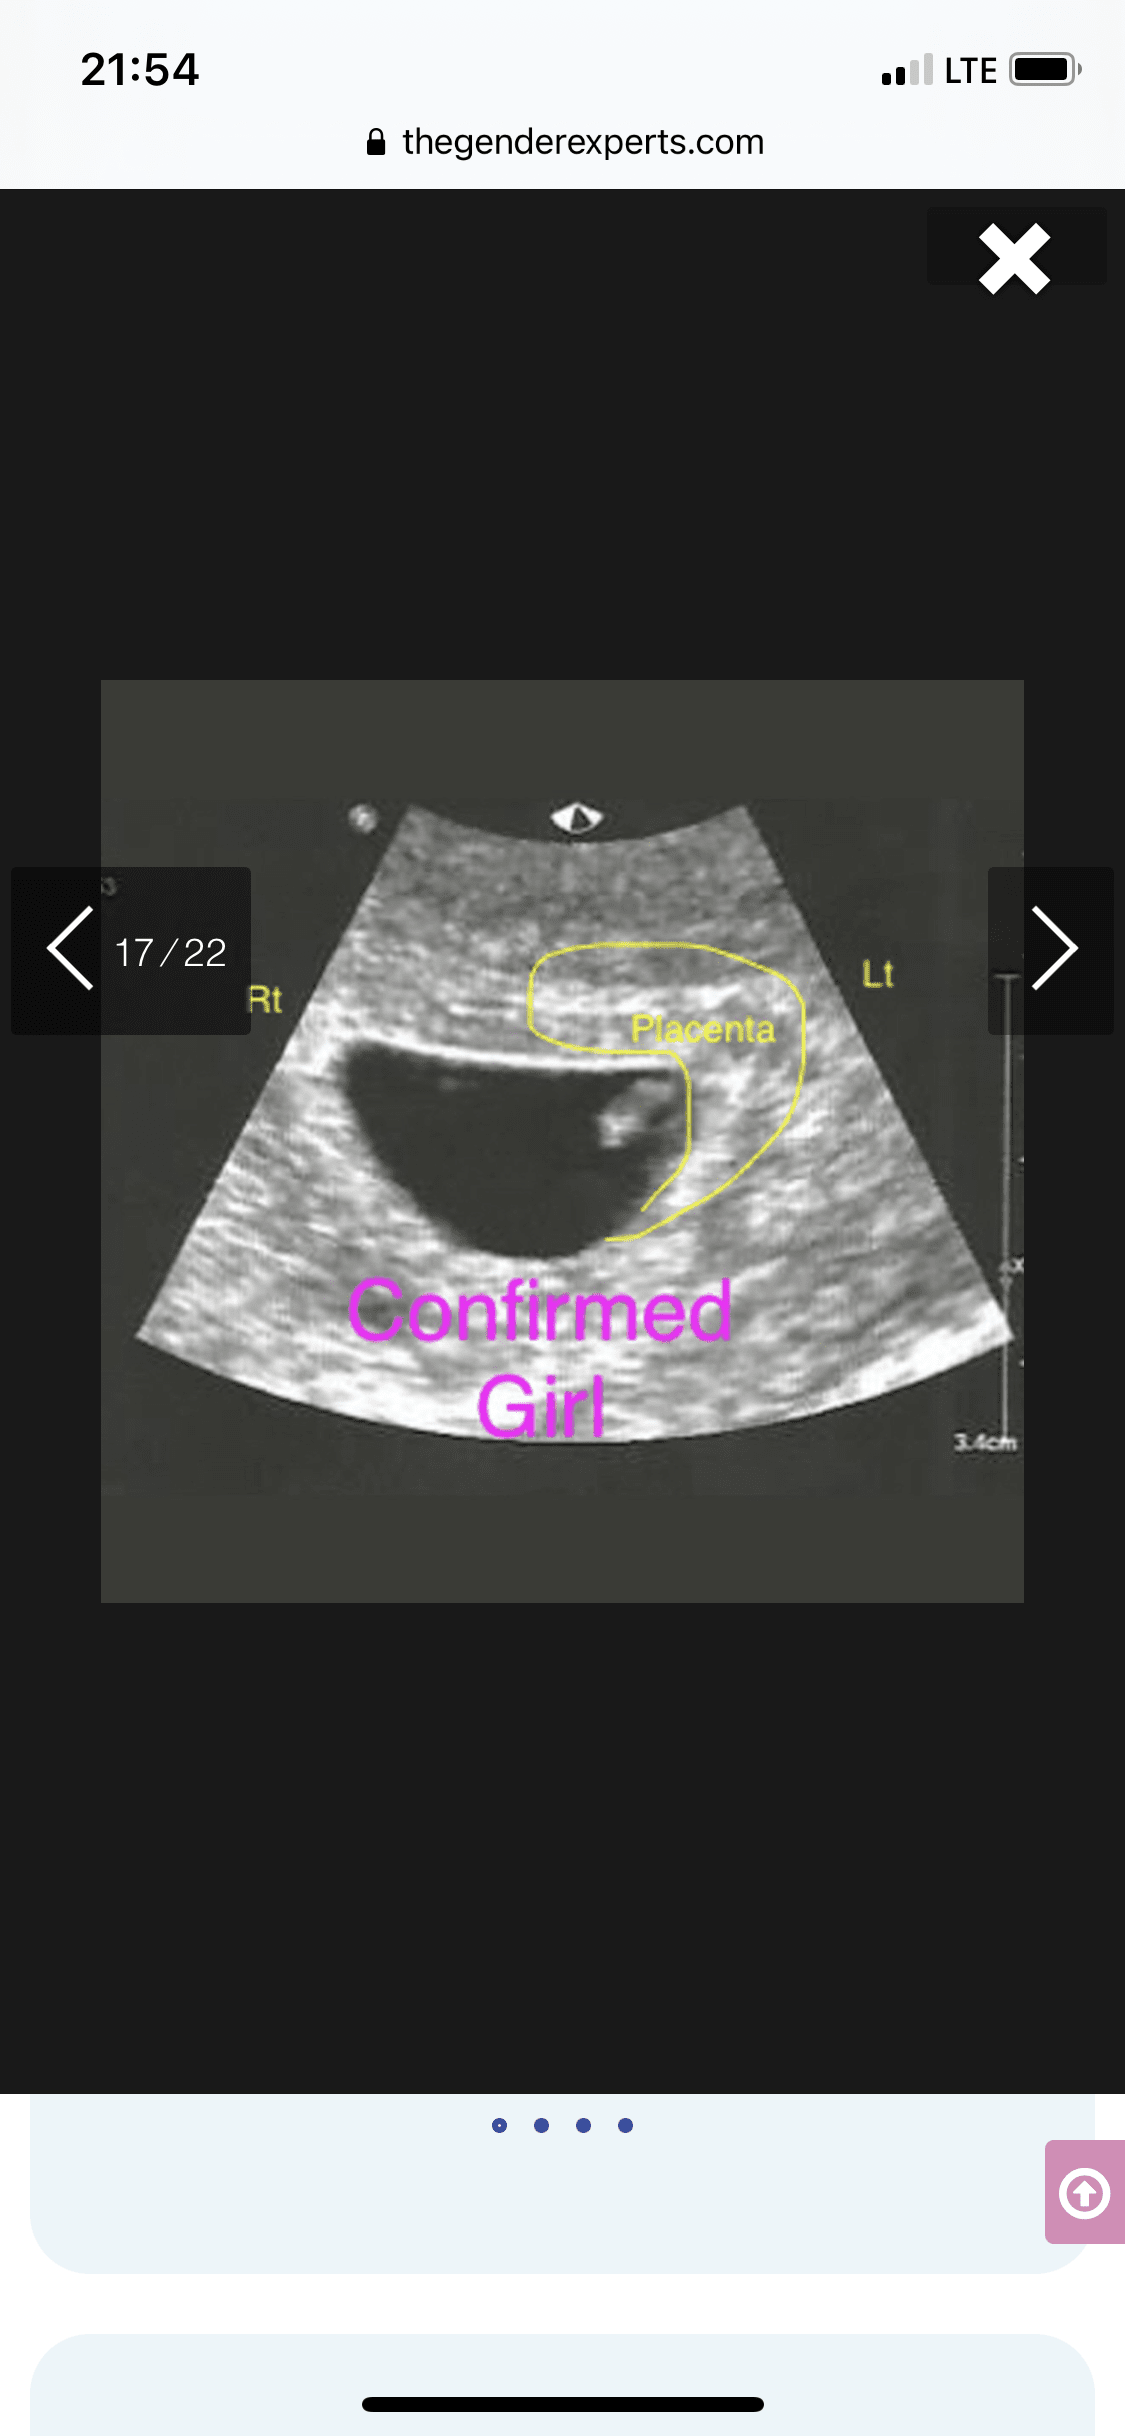

Tak dokładnie chodzi o położenie kosmowki z której potem wytworzy się łożysko. Metoda się sprawdza tak jak mówisz 50/50Aaa pytałam wtedy o położenie kosmowki.